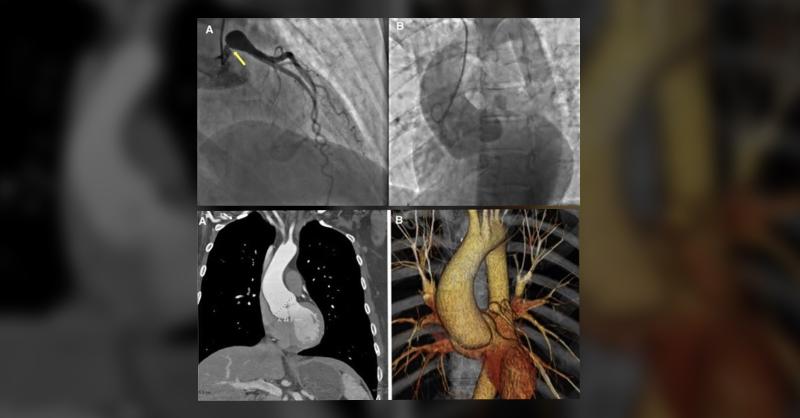

A team of cardiologists incidentally discover ectatic aortic root in a 48-year-old woman during evaluation for a neck mass. As part of pre-operative evaluation for aortic root replacement, left heart catheterization was performed that revealed a left main coronary artery aneurysm. Family history was significant for aortic aneurysms, sudden cardiac